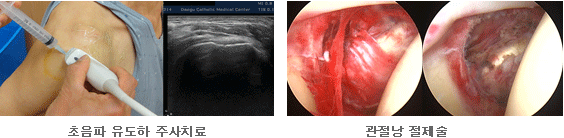

경도의 충돌증후군이 있으면 휴식과 투약 그리고 물리치료를 통해 염증을 완화시키고 위축된 근육의 근력을 회복시킬 수 있다. 통증을 유발할 수 있는 활동은 통증이 없을 때 서서히 재개해야 한다. 필요 시 주사치료로써 종창과 염증을 줄일 수 있으나, 약제와 주사횟수 및 시술 방법 등에 유의하여야 한다. 6개월 이상의 보존적 치료에도 증상의 호전이 없을 경우 관절경을 이용한 수술적 치료를 시행할 수 있다. 회전근 개의 완전파열이 있으면 수술적 치료로 건을 봉합하는 것을 일차적으로 고려할 수 있다. 수술방법의 선택은 증상의 정도, 환자의 건강상태, 견관절의 활동량 등에 의해 결정된다. 젊고 활동량이 많은 사람의 경우 대부분 건의 봉합이 필요하나, 활동양이 적은 노인의 경우 보존적 치료로도 증상의 완화가 되는 경우가 많으며, 필요 시 부분적 봉합만으로도 좋은 결과를 보기도 한다